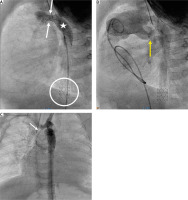

Figure 3

Percutaneous arterial duct stent deployment and banding balloon plasty. A – Pulmonary artery angiography in lateral view in patient 6 following Palmaz Genesis 8 mm/12 mm stent deployment into the arterial duct (white star) with proximal duct stenosis (white arrow). B – Left pulmonary artery band balloon plasty with an indentation at the tight band (yellow arrow). White stars indicate 2 wide stents implanted into the stenotic arterial duct. C – Right pulmonary artery band balloon plasty with an indentation at the tight band (yellow arrow)